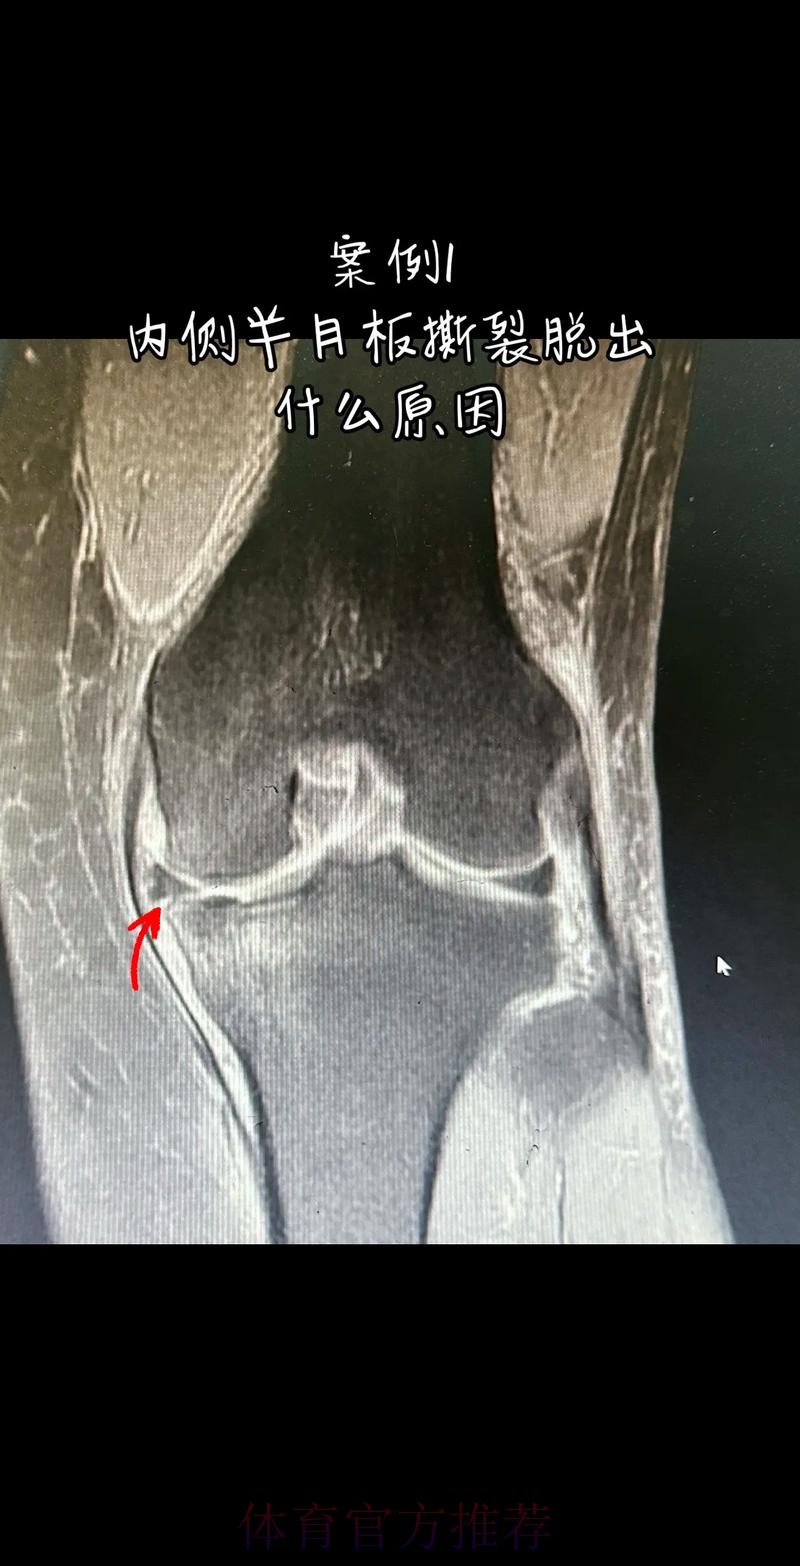

官方:阿拉巴左膝内侧半月板撕裂 预计伤缺6-8周

这条“官方 阿拉巴左膝内侧半月板撕裂 预计伤缺6-8周”的声明一出 不只是伤病通告那么简单 它背后牵动的是皇马后防体系的重塑 奥地利国家队备战计划的调整 以及一名顶级后卫职业生涯中一次关键的健